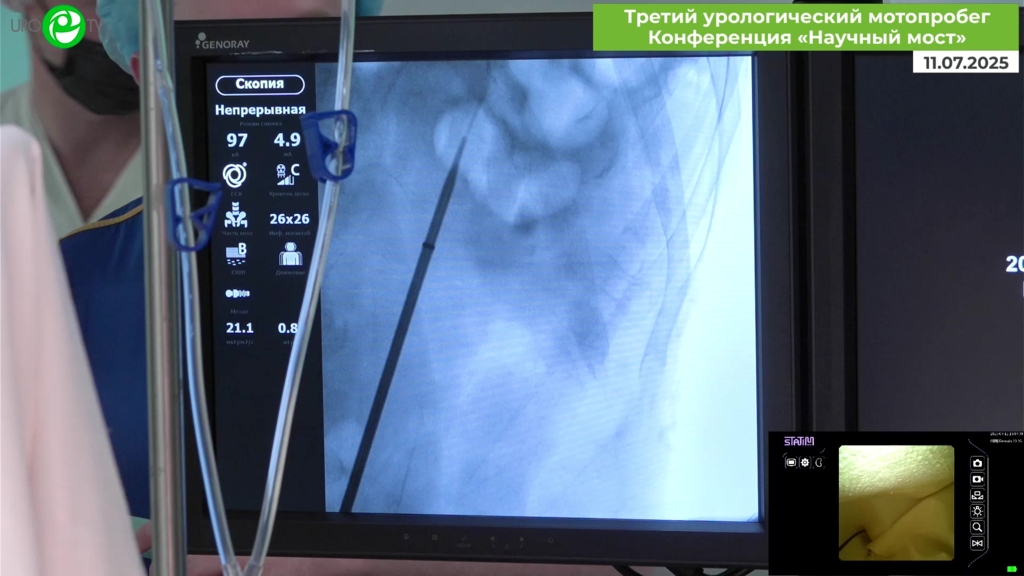

Байков Н.А. - Ретроградная интраренальная хирургия

18 июл 2025

Мочекаменная болезнь